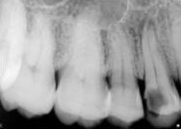

antes depois